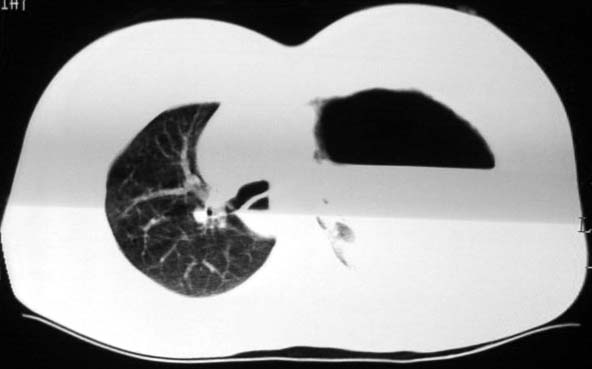

标题: CT5517:女性、24岁,反复胸痛、气促不能平卧半月。 [打印本页]

标题: CT5517:女性、24岁,反复胸痛、气促不能平卧半月。

左肺可见二个含气或液气的囊状影,左肺段支气管、左肺动脉显示不清,纵隔右移,考虑:左肺支气管肺囊肿,左肺发育不良,纵隔疝。

左侧气液腔与胃腔影相连,考虑膈疝。钡餐检查有助于诊断。

我看这是膈疝,在纵隔窗第六\\七幅图像上可见胃粘膜影,再者可见两个腔影,这在液气胸是不会有的.

左侧气液腔与胃腔影相连,考虑膈疝。钡餐检查有助于诊断

左侧气液腔与胃腔影相连,考虑膈疝。口服urografin检查有助于诊断。